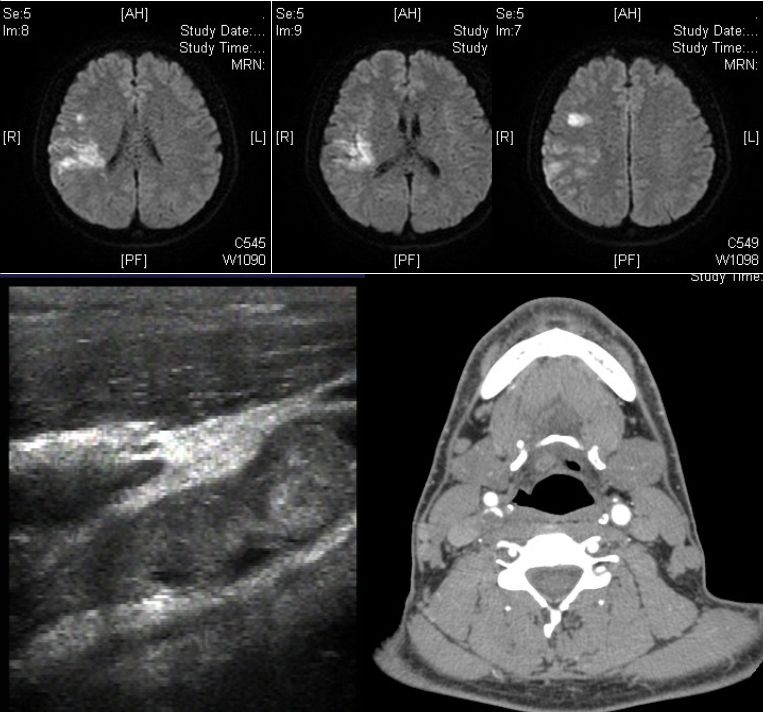

患者,21岁女性,患者3小时前做某手术后突 发右侧肢体乏力、意识不清。

发病24小时磁共振:

答案:脑型脂肪栓塞综合征。患者做了自体脂肪填充术。脂肪栓塞综合征(fat embolism syndrom,FES)是指直径为10~40μm的血管内脂肪颗粒阻塞血管腔而引起的一系列病理生理改变的临床综合征。FES常发生于骨创伤及骨手术病人。FES潜伏期为6~24h,FES 的典型三联征为低氧血症、意识障碍和瘀斑。